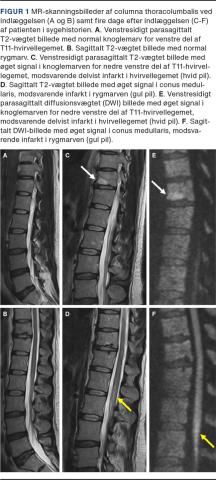

Arbejdsdiagnosen var cauda equina-syndrom, og indledningsvis var MR-skanning af columna lumbalis normal (Figur 1A og B). Patienten blev overflyttet til neurologisk regi med differentialdiagnoserne Guillain-Barrés syndrom, transversel myelitis og RI. Rutineblodprøver og cerebrospinalvæske (CSV)-analyse var normale. Patienten udviklede tiltagende brændende og jagende smerter med god effekt af morphin og gabapentin.

Med fortsat mistanke om medullær affektion blev udredningen udvidet den fjerde dag efter indlæggelsen med MR-skanning af cerebrum samt columna thoracalis og lumbalis, som viste nytilkomne forandringer centralt i conus medullaris på niveau Th12/L1 (Figur 1D og F) og i den anteriore corpus vertebrae Th11 (Figur 1C og E), næsten sikkert forenelige med RI hhv. knogleinfarkt. Man påbegyndte pladehæmmerbehandling og udredte med telemetri samt koagulopati- og vaskulitisblodprøver, som var upåfaldende. Efter tre måneders rehabilitering kunne patienten gå uden brug af hjælpemidler, og der var ikke længere afføringsinkontinens, men vedvarende neuropatiske smerter.